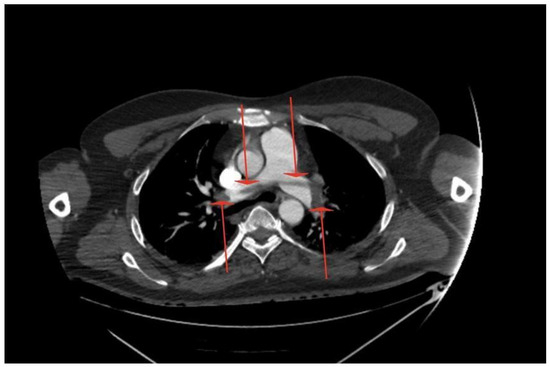

Massive Central Pulmonary Embolism with Riding Embolus and Concomitant Aortic Arch Embolism—Should We Diagnose Patients Earlier for Blood Clotting Disorders? Case Report

2. Case Report